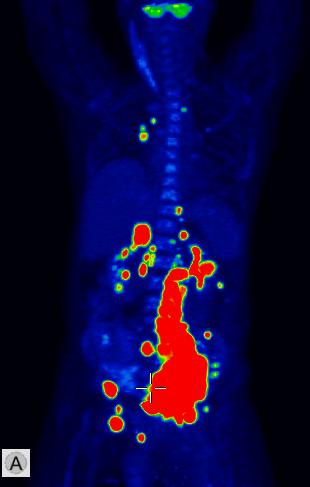

The most common clinical use of FDG-PET is in the form of whole-body scan, with oncologic indications. The majority of malignant tumors operate with higher energy consumption and show an increased glucose metabolism, consequently an increased uptake of FDG. The grade of malignancy is usually proportional to the rate of uptake. This method is useful in oncologic diagnostics, since it is capable to differentiate benign lesions from malignant ones. Whole-body PET imaging is capable to detect the primary tumor with local nodal metastases as well as distant metastatic lesions (staging) in one examination. (Figure 10.)

Test iframe

a

Image

b

c

d

10. Ewing’s sarcoma in the right humerus. Staging FDG PET-CT. PET Maximum Intensity Projection (MIP) image (a), transversal (b,c) and coronal (d) plane fused PET-CT images. Multiplex metastatic process with nodal, lung and bone involvement.